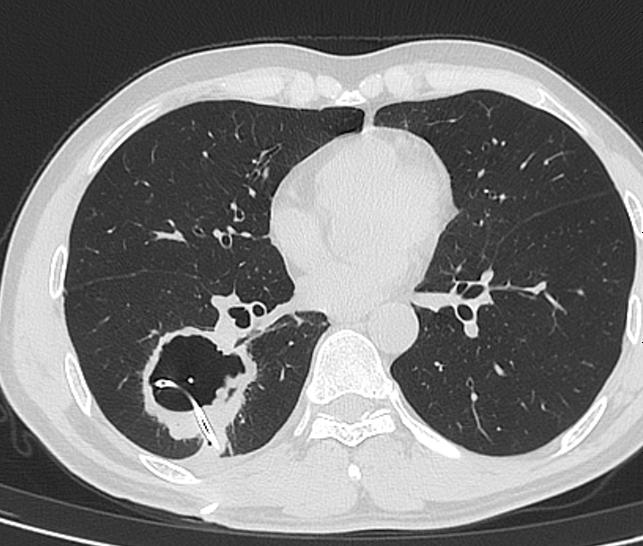

这个引流管放进去,啥都没有引流出来,还导致了少量气胸。

图06

患者转我院,手术切除空洞,病例:肺鳞癌。